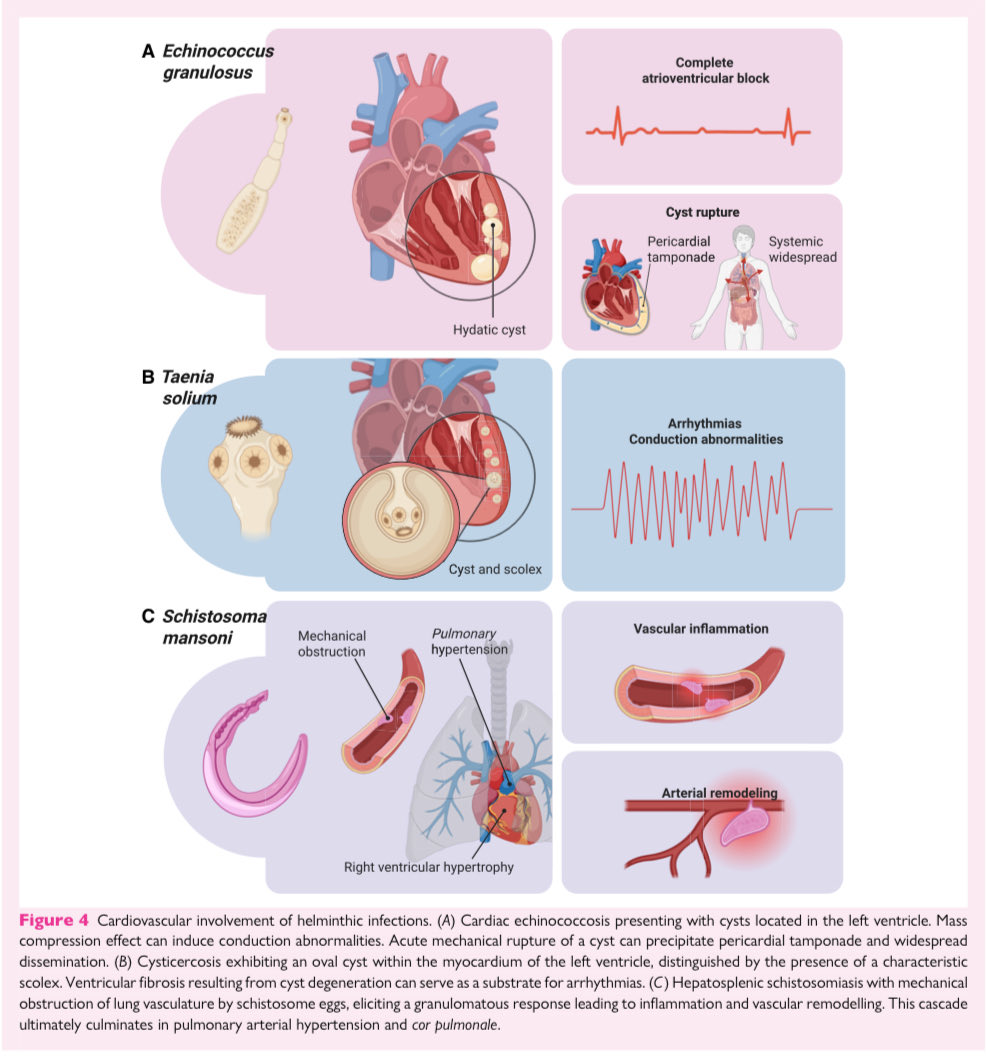

🗺️ Cardiac imaging in patients with tropical diseases: a scientific statement @ESC_Journals #Cardiology #CardioEd #echofirst #FOAMed

🗺️ Cardiac imaging in patients with tropical diseases: a scientific statement @ESC_Journals #Cardiology #CardioEd #echofirst #FOAMed